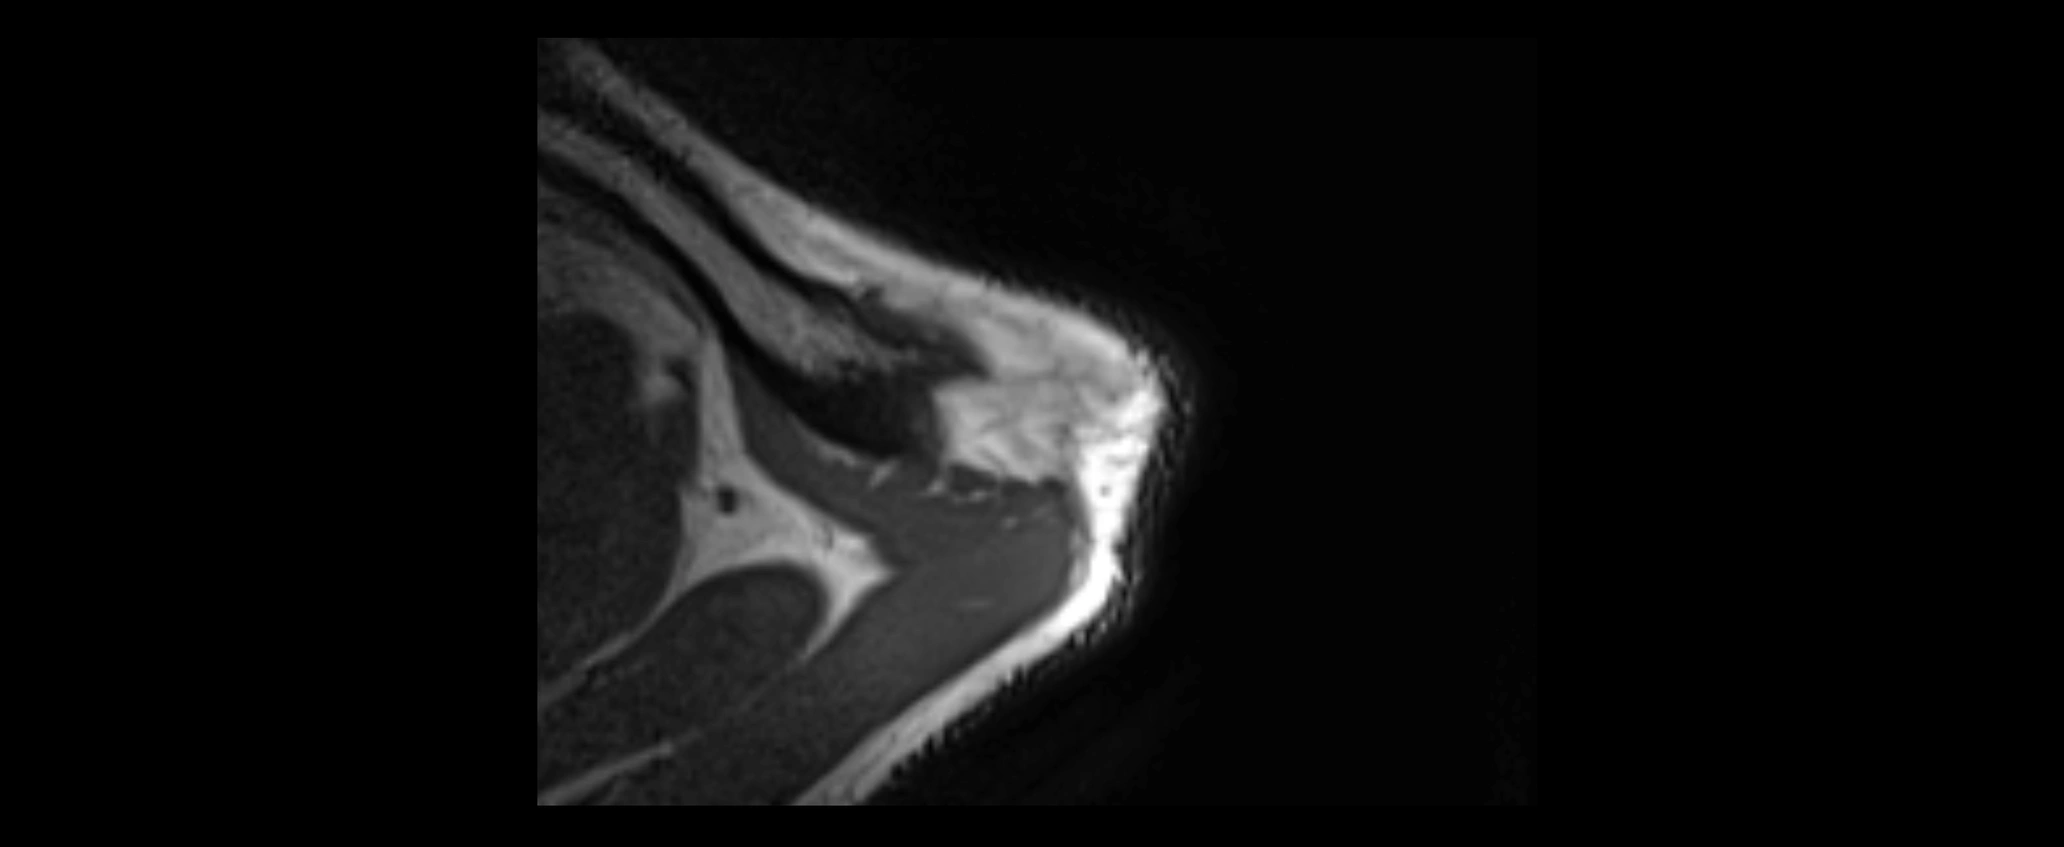

CT image

image